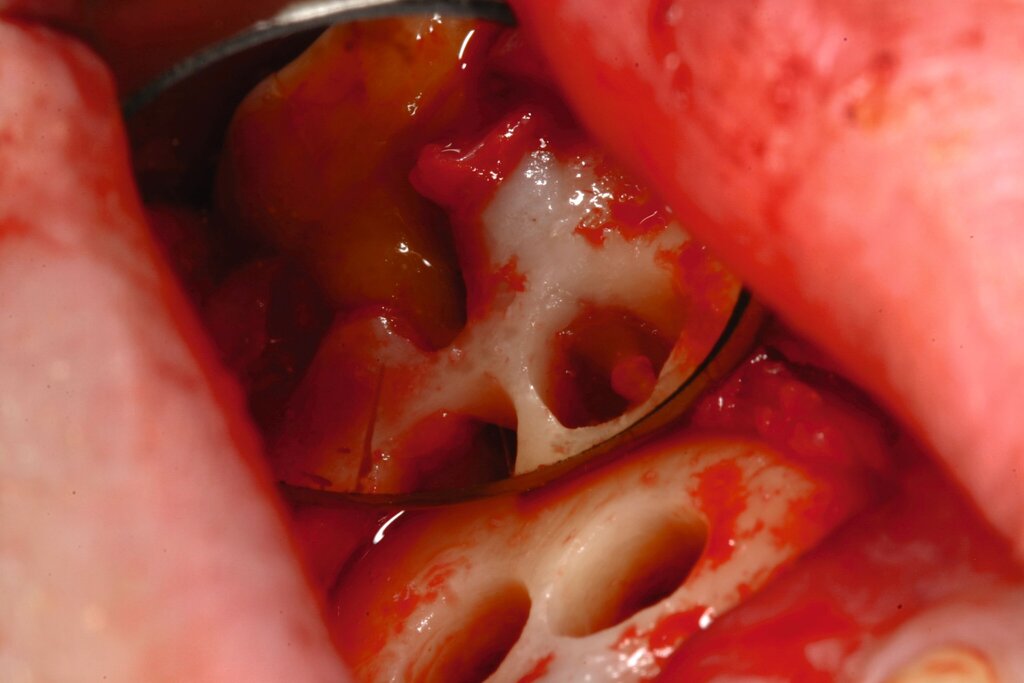

Bezüglich der Zahnlokalisation zeigen eigene Zehn-Jahres-Daten signifikante Unterschiede zugunsten des Oberkiefers. Bei der differenzierteren Betrachtung von Frontzähnen, Prämolaren und Molaren zeigte der paarweise Vergleich signifikante Unterschiede zwischen den Molaren und den Frontzähnen sowie den Molaren und den Prämolaren. Die Unterschiede zwischen Frontzähnen und Prämolaren waren nicht signifikant [Kreisler et al., 2018]. Bei diesem Phänomen handelt es sich möglicherweise mitunter um ein statistisches Problem. Betrachtet man nämlich jede einzelne Wurzel als Lokus des potenziellen Scheiterns, steigt natürlich das Gesamtrisiko bei einem mehrwurzeligen Zahn. Das Vorhandensein von Isthmen als Ursache wurde in der Literatur diskutiert [Kim et al., 2016]. Allerdings stellt das Erkennen von diesen und deren Einbeziehen in die Präparation und Abdichtung heutzutage eigentlich eine Selbstverständlichkeit dar (Abbildung 4). Gleiches gilt für die Berücksichtigung der palatinalen Wurzel bei Oberkiefermolaren.